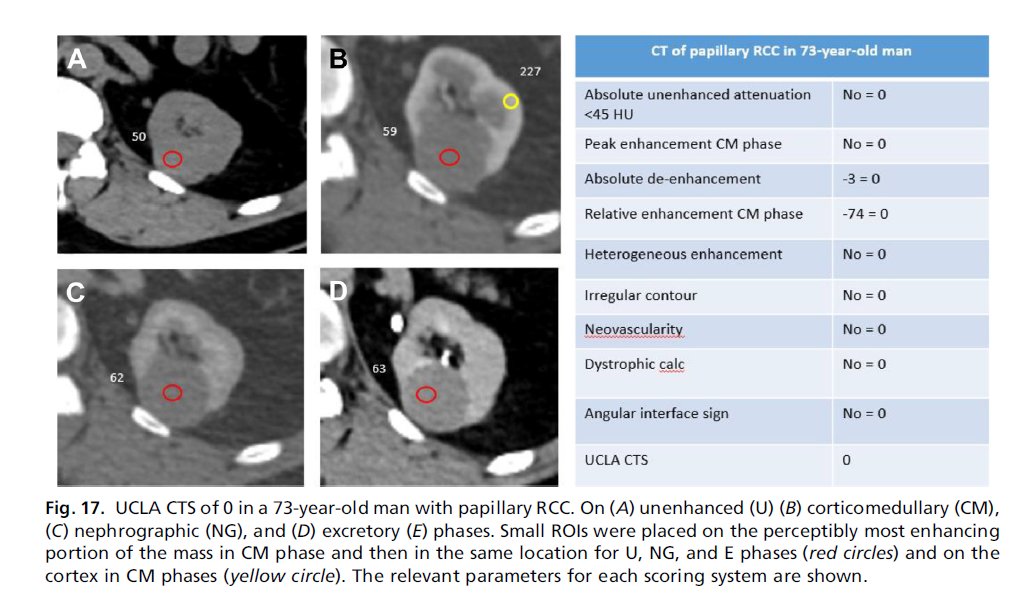

Radiologist’s Disease: Imaging for Renal Cancer sciencedirect.com/science/articl… 🔵A must read article on imaging-based characterization of renal masses by Dr. Alex Chung and Dr. Steven S. Raman MD, FSAR, FSIR 👍Thank you for this nice paper #radiology #medtwitter #CancerResearch